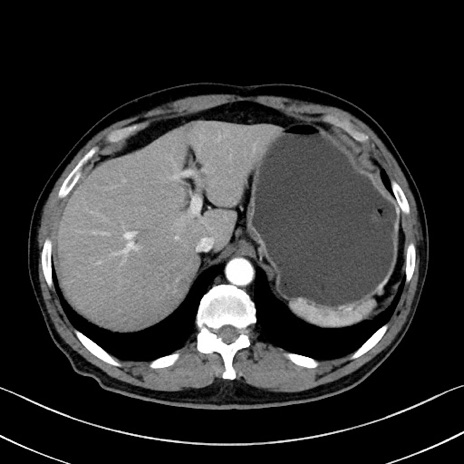

症例35(横断像)

【症例】70歳代 男性

【主訴】腹部膨満、嘔吐

【現病歴】昨日より腹部膨満感出現。本日増悪し、仙痛出現。嘔吐あり、受診。

【既往歴】糖尿病、胆摘後

【身体所見】BP 149/80mmHg、HR 74/min、BT 35.9℃、腹部:膨満、軟、圧痛なし。腸雑音減弱あり。上腹部正中切開瘢痕あり。

【データ】WBC 13500、CRP 1.72